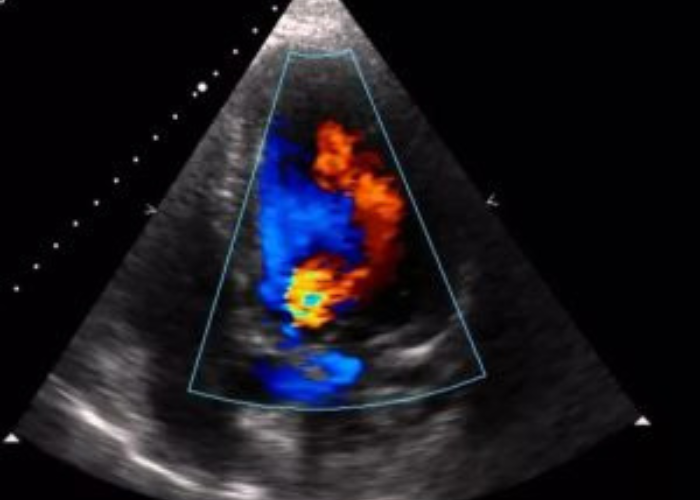

The Colour Doppler component adds a visual layer showing blood flow in real-time. It displays the speed and direction of blood movement using color-coded images, which is critical in detecting turbulent or reverse blood flow, indicating problems such as valve leakage (regurgitation), narrowing (stenosis), or congenital defects like septal holes.